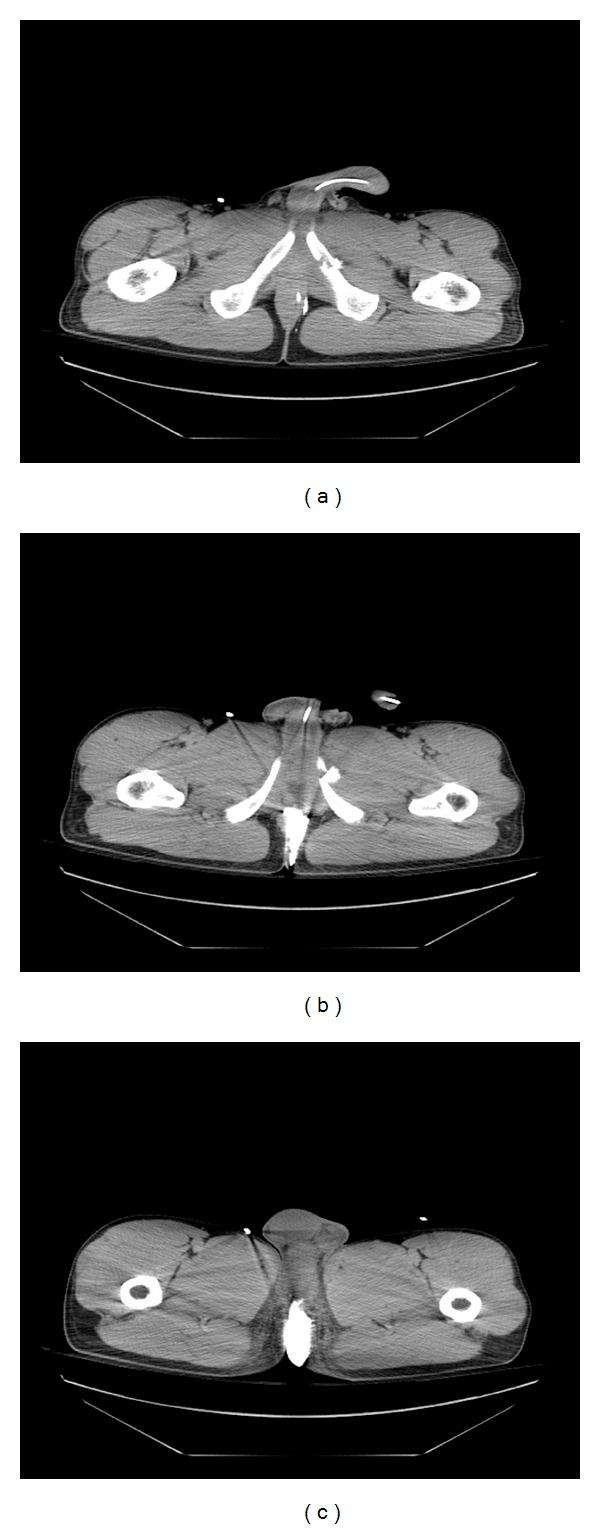

Posterior urethra rupture: contrast-enhanced computed tomography scan and urethrocystography demonstrations.

In the follow-up study of patients with pelvic fractures, rupture of the posterior urethra is registered in 3-25% of cases (Koraitim et al., 1996). The diagnostic gold standard for the assessment of hemodynamically stable trauma patients is contrast-enhanced CT scan, especially helical CT. Nevertheless, simultaneous suprapubic cystography and ascending urethrograms (the so-called up-and-downogram) are the investigation of choice in assessing the site, severity, and length of urethral injuries. (Carlin and Resnick, 1995) This paper discusses the evaluation and diagnosis of urethral injury in multiple-trauma patient.